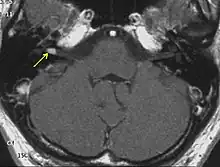

The so-called acoustic neuroma of NF2 is in fact a schwannoma of the nervus vestibularis, or vestibular schwannoma. The misnomer of acoustic neuroma is still often used. The vestibular schwannomas grow slowly at the inner entrance of the internal auditory meatus (meatus acousticus internus). They derive from the nerve sheaths of the upper part of the nervus vestibularis in the region between the central and peripheral myelin (Obersteiner-Redlich-Zone) within the area of the porus acousticus, 1 cm from the brainstem.

NF2 is a genetically transmitted condition. Diagnosis is most common in early adulthood (20–30 years); however, it can be diagnosed earlier. NF2 can be diagnosed due to the presence of a bilateral vestibular schwannoma, or an acoustic neuroma, which causes a hearing loss that may begin unilaterally.[15] If a patient does not meet this criterion of diagnosis, they must have a family history of NF2, and present with a unilateral vestibular schwannoma and other associated tumors (cranial meningioma, cranial nerve schwannoma, spinal meningioma, spinal ependymomas, peripheral nerve tumor, spinal schwannoma, subcutaneous tumor, skin plaque). This being said, more than half of all patients diagnosed with NF2 do not have a family history of the condition.[15] Although it has yet to be included into clinical classification, peripheral neuropathy, or damage to the peripheral nerves, which often causes weakness, numbness and pain in the hands and feet, may also lead to a diagnosis of NF2. In children, NF2 can present with similar symptoms, but generally causes "visual disturbances (cataracts, hamartomas), skin tumors, mononeuropathhy (facial paresis, drop foot), symptomatic spinal cord tumors, or non-vestibular intracranial tumors".[15]

Bilateral vestibular schwannomas are diagnostic of NF2.[16]